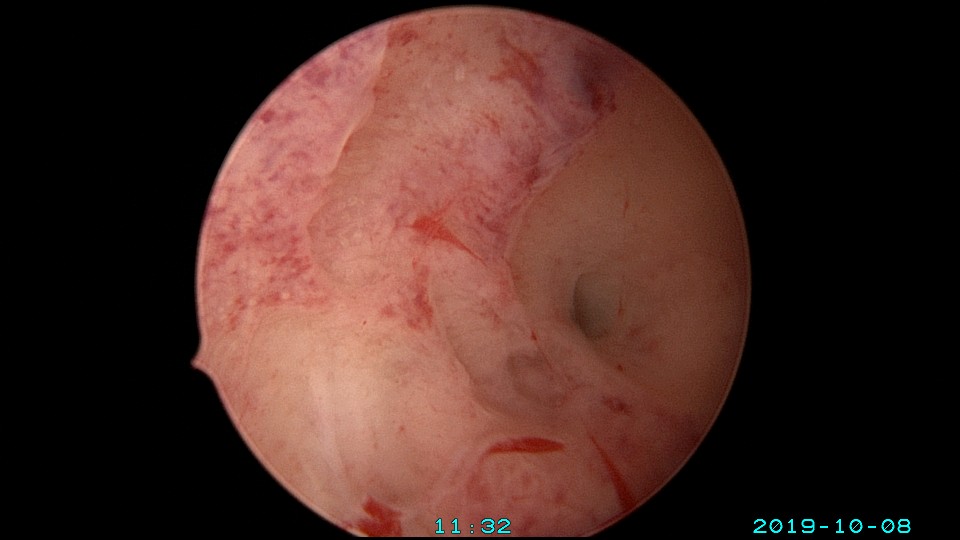

患者27岁,G2P0,人流1次,孕8周胎停清宫1次,绵阳市某医院造影发现宫腔粘连1+月,2019年10月初我院宫腔镜探查,发现宫腔右侧粘连,左侧输卵管开口可见,单极电切分粘,恢复宫腔形态,显露右侧输卵管开口。2019年10月底宫腔镜二探取球囊,宫腔形态正常,双侧输卵管开口可见。2021年10月自然妊娠,稽留流产,我院宫腔镜取胚,2022年再次自然妊娠,足月分泌。现33岁,G4P1。